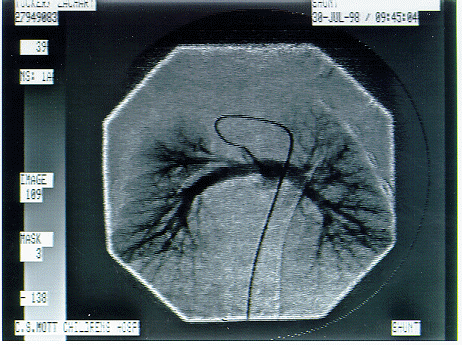

The Heart Cath Showed Larger Pulmonary Arteries!